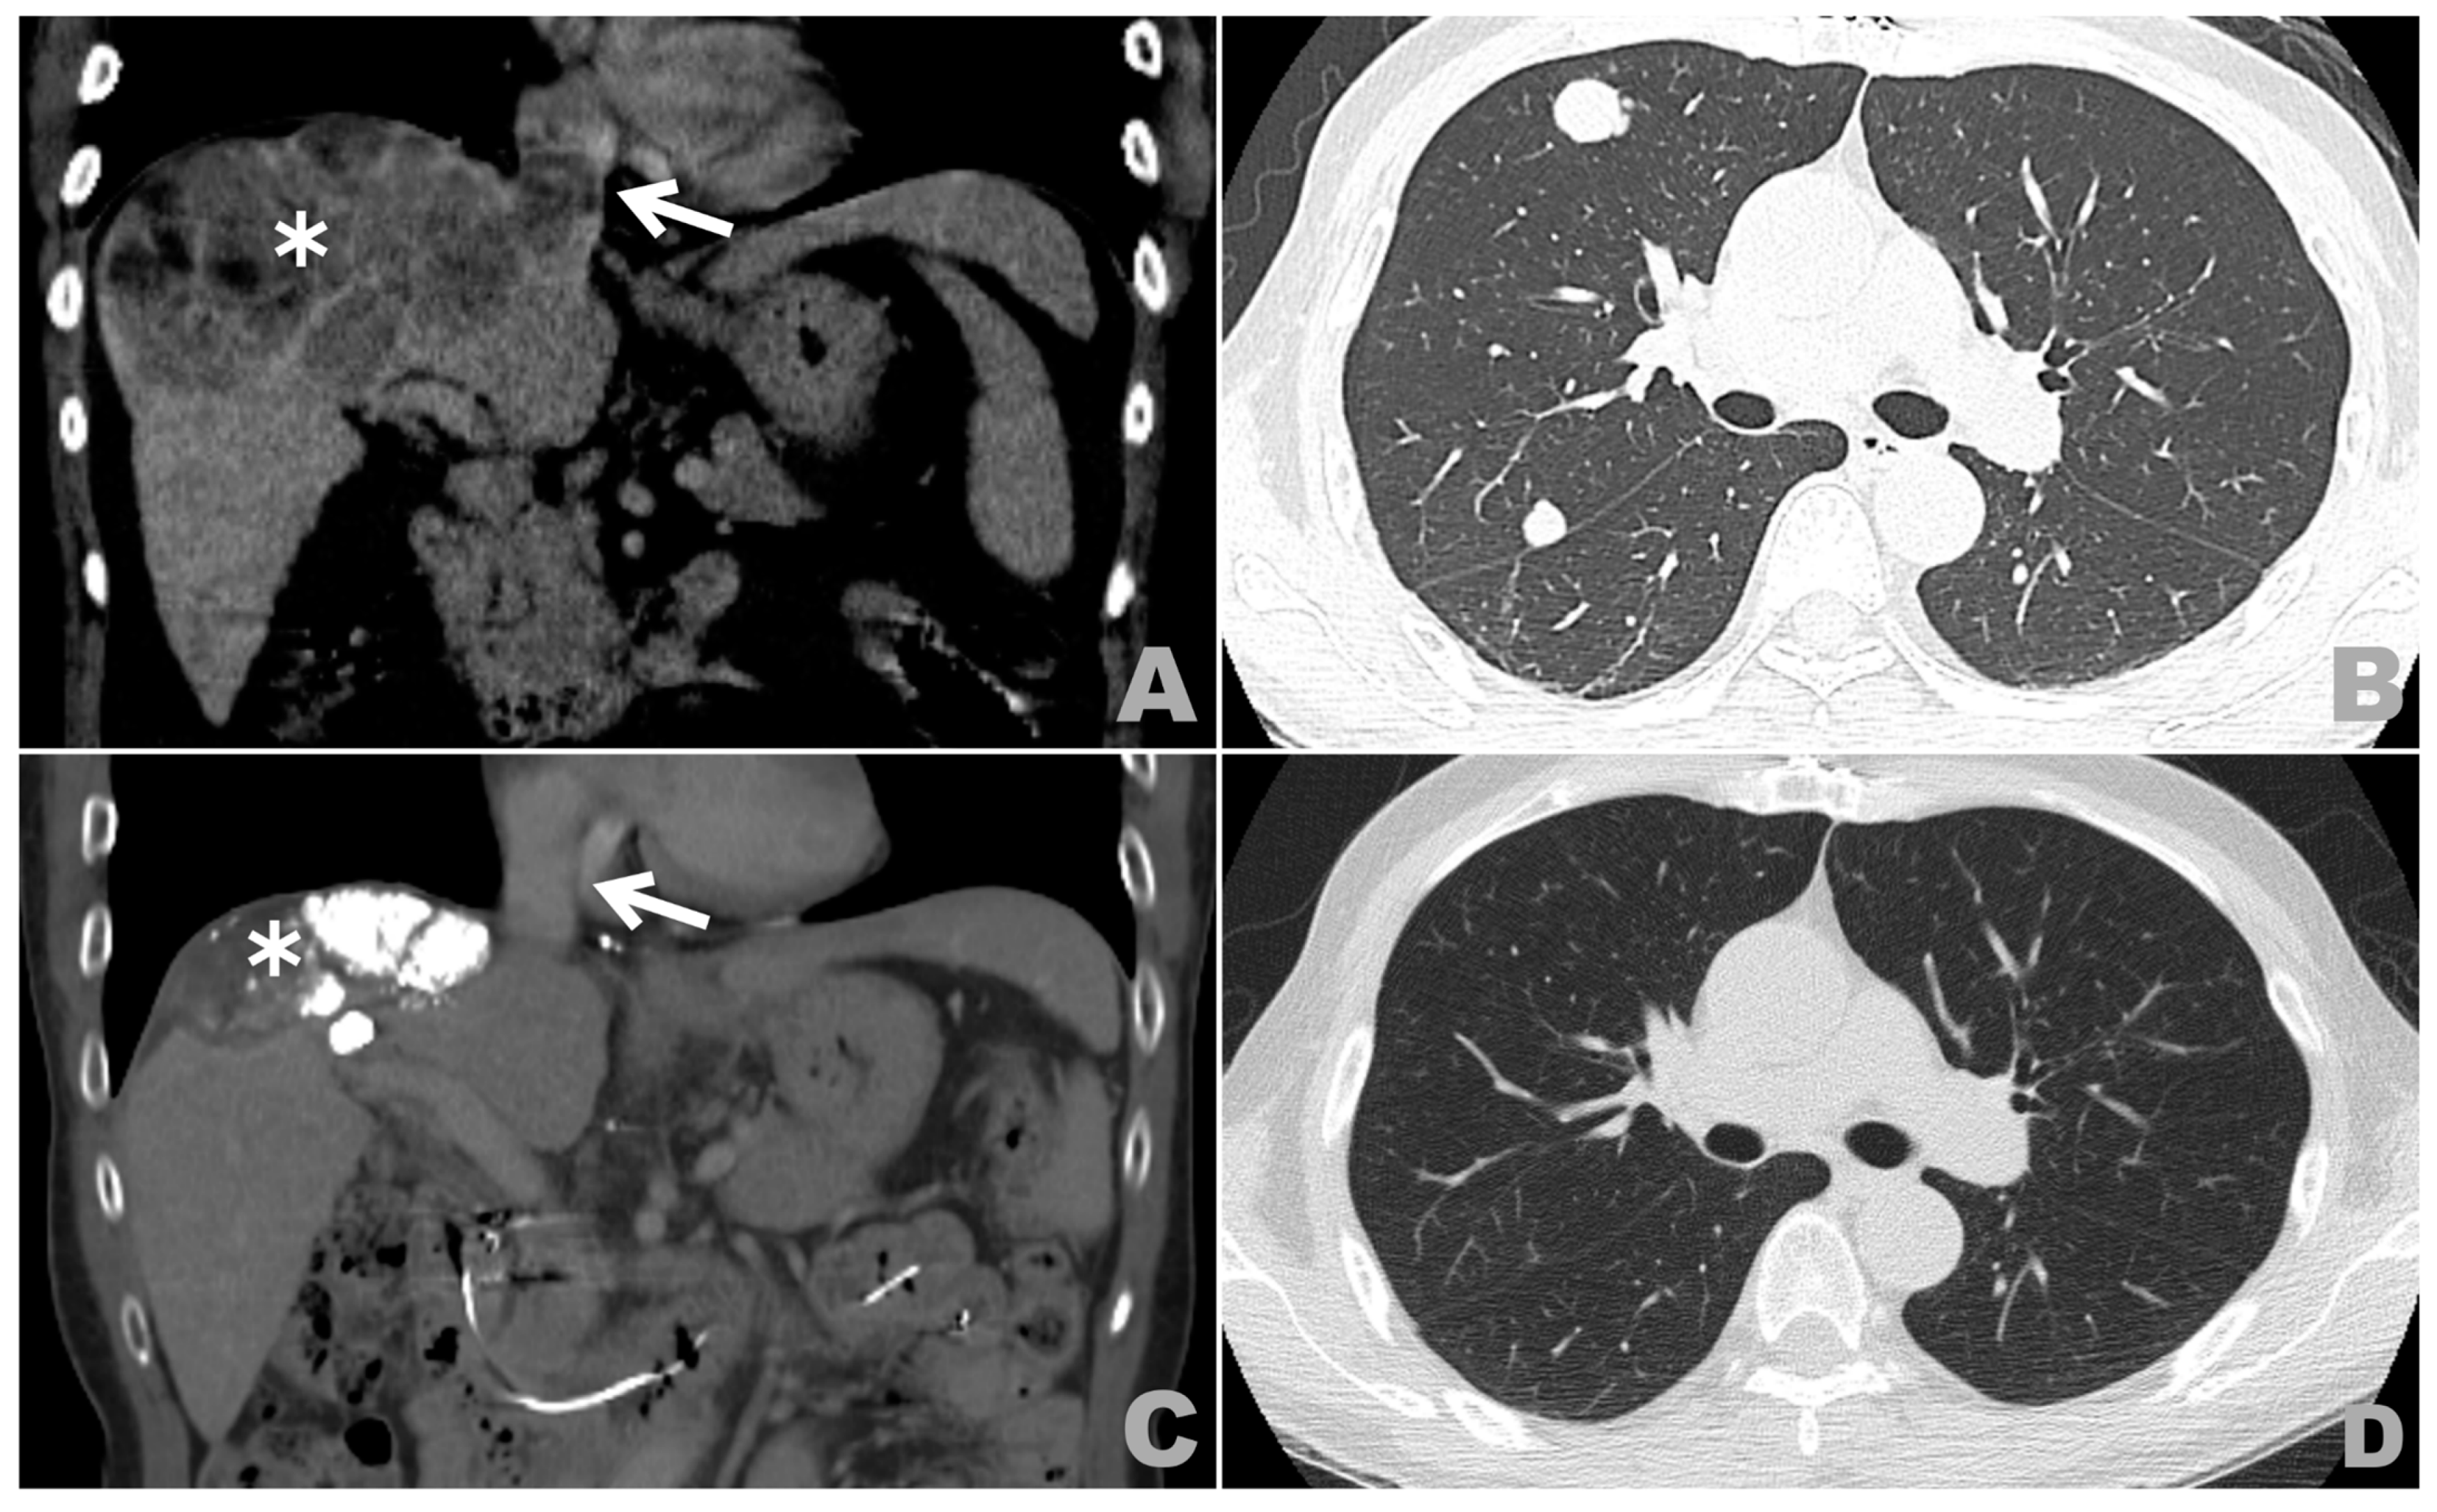

Complete Response in Metastatic Hepatocellular Carcinoma with Cardiac and Lung Involvement via Multimodality Treatment

2. Case Presentation